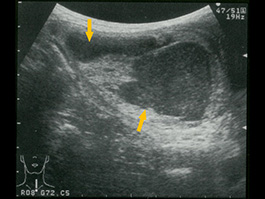

橋本病の甲状腺横断像。甲状腺は腫大し丸みを帯びていて、辺縁は凸凹している。内部エコーは低く不均一で、線維化を反映するといわれている線状高エコーが目立つ。 |